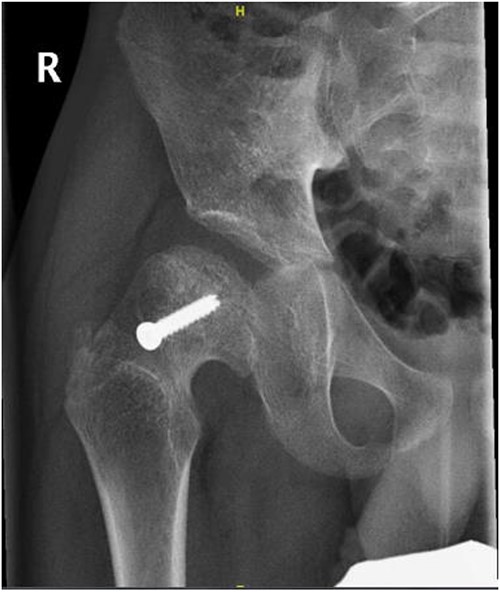

A 5-year-old independent ambulatory Middle Eastern boy with CP who was born preterm and developed grade III intraventricular haemorrhage and periventricular leucomalacia and was on AEDs, including valproic acid (VPA) and levetiracetam (LEV), for >3 years and was controlled over the last year (no history of seizure attack) presented to the emergency room (ER) with right hip pain and inability to bear weight for 4 weeks; the patient had no history of fever or trauma. Physical examination shows a thin, the weight is 12 kg, the height is 101 cm, vital signs within the normal range, tenderness over the right hip, and external rotation of the right hip, with restricted hip mobility. A radiological study was performed ~3 months before the patient presented to the ER for follow-up examination of a left hip coxa valgus deformity with no apparent abnormalities in the right hip (Fig. 1). Initial imaging studies conducted in the ER showed an anterior–posterior view of the pelvic radiograph, revealing Klein’s line [13] not intersecting the capital femoral epiphysis (Fig. 2), and frog-leg lateral view radiograph of the right hip (Fig. 3) confirmed SCFE and Southwick’s slip angle [13] of ~50° (moderate). Laboratory findings were clear for endocrine and renal diseases or infection, except for low vitamin D (total 25-OH Vitamin D: 43.4 nmol/L), suggesting vitamin D insufficiency. The diagnosis was confirmed with clinical and radiological studies as right-sided unstable SCFE requiring surgery. Surgical intervention was performed with percutaneous in situ fixation using a single fully threaded 4.5-mm cannulated screw (Fig. 4). Postsurgical rehabilitation included non-weight-bearing right lower extremities for 6 weeks. Regular follow-up with serial radiology studies showed stable fixation with no migration of screw or further slippage at 6 weeks (Fig. 5) and 3 (Fig. 6), 15 (Fig. 7), and 36 months (Fig. 8). During follow-up, a painless range of motion in the right hip was observed, with full weight-bearing and resumption of his usual activities with no complaints.

Right hip anterior–posterior radiograph, 36 months following post-operative fixation.